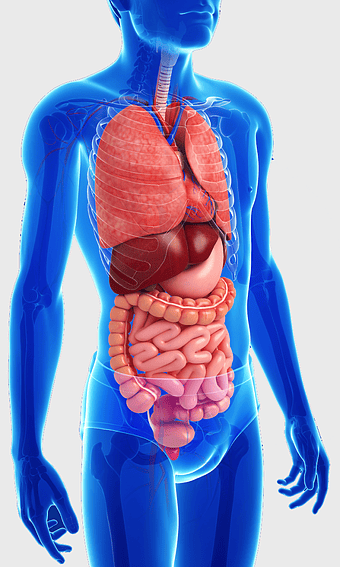

Human internal organs illustration, heart and lung anatomy, kidney and liver diagram, brain and stomach structure, medical organ chart, human body systems visual, educational anatomy graphics, PNG

- human internal organs illustration

- heart and lung anatomy

- kidney and liver diagram

- brain and stomach structure

- medical organ chart

- human body systems visual

- educational anatomy graphics

female human organ model, human digestive system anatomy, gastrointestinal tract illustration, liver and stomach diagram, medical education visuals, anatomical study aids, human body internal structures -

human anatomy illustration, human organ system diagram, human body internal organs, human digestive system, anatomical chart, medical illustration, physiological diagram -